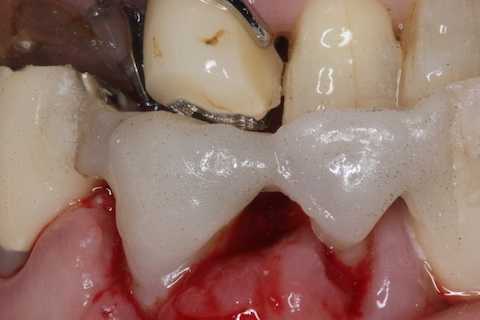

前回 ​のつづきで、再植と化粧をする。さすがに歯なしでは寂しい。

あとは接着固定しながら、歯冠を再建していく。